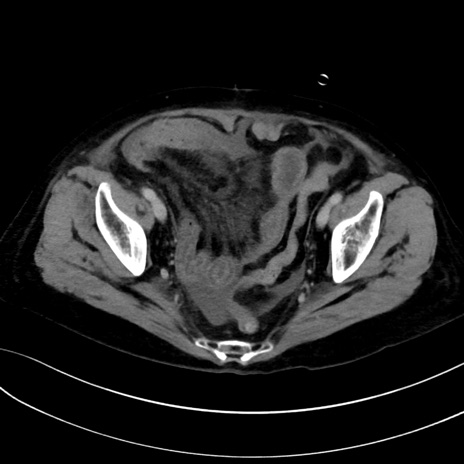

症例13 CT(横断像)1日半後